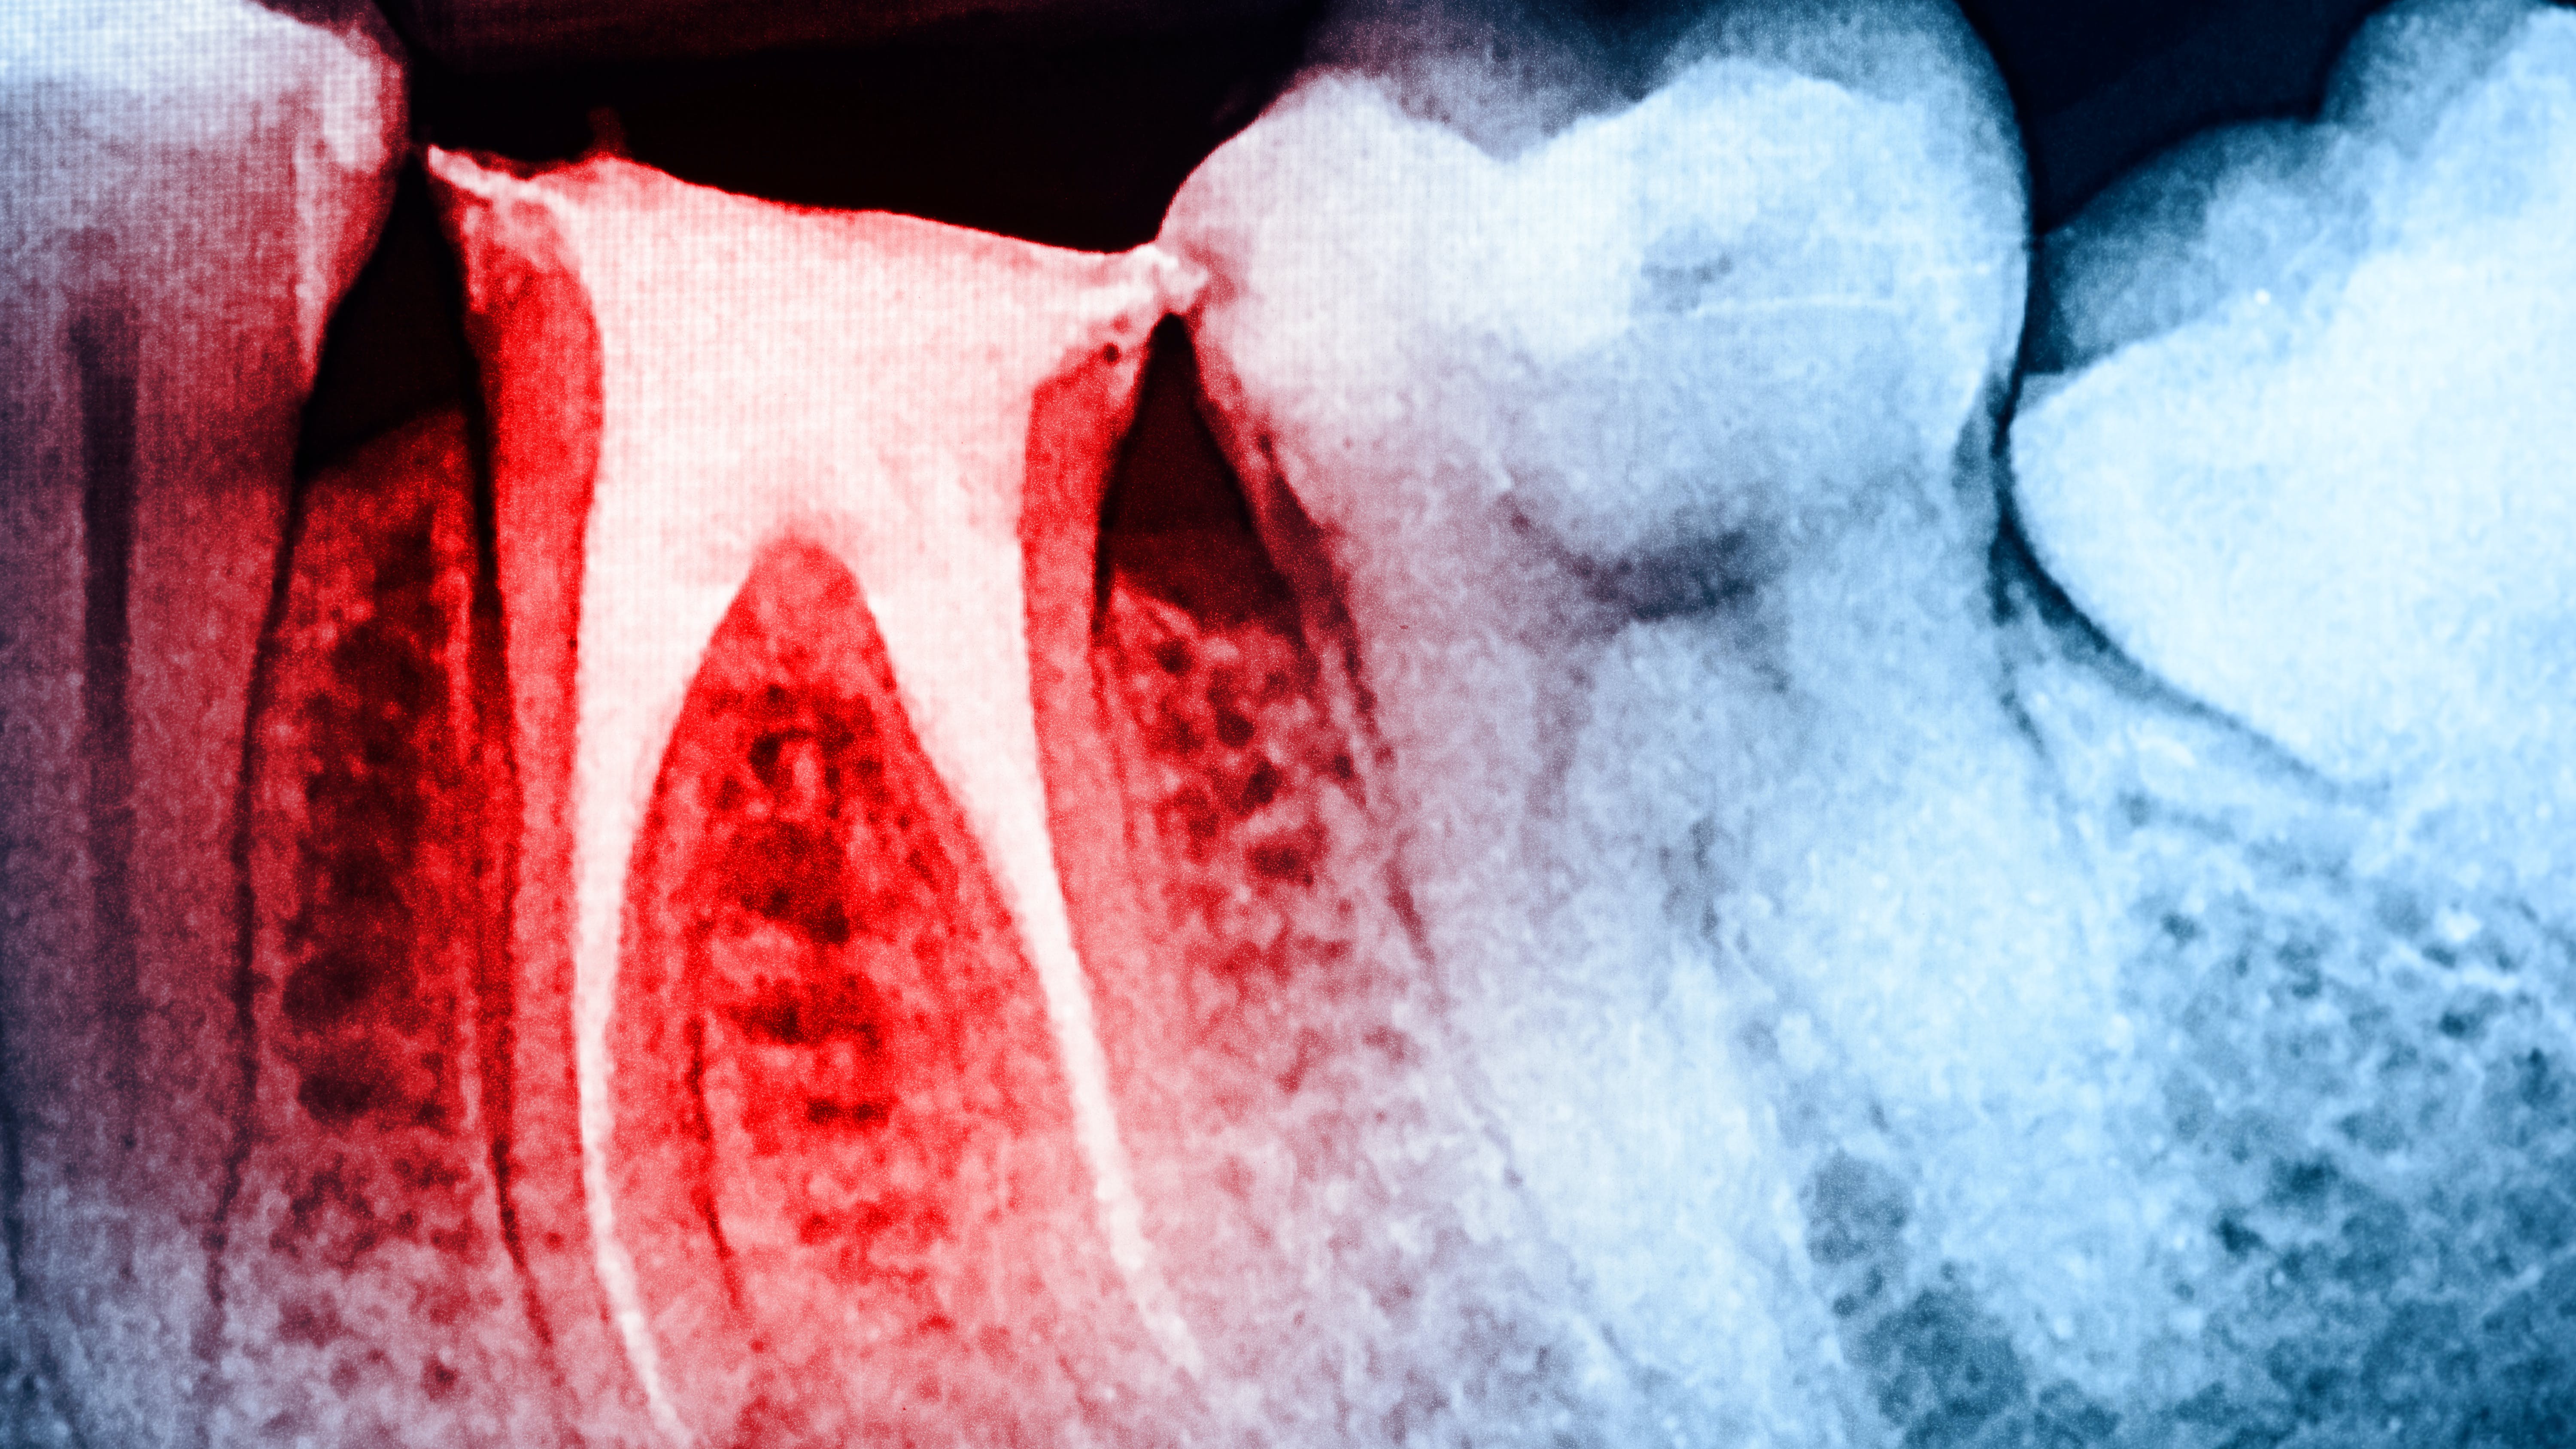

Root fracture is a common source of pain after root canal treatment and is of particular concern since it may be hard to diagnose (figure 1).5 Although new technologies such as three-dimensional imaging and microscopes have increased diagnostic ability, vertical fractures can still be hard to ascertain. Isolated periodontal pockets and a history of sharp pain that progresses to a dull throbbing pain upon mastication/palpation are common signs of fracture. Other common risk factors for fracture include: the lower second molar (most likely tooth to fracture), parafunctional habits including clenching/bruxism, large amalgam restorations, thermal injury, psychological stress, teeth with existing erosion, abrasion, and/or abfraction. A fractured tooth may need to be extracted to alleviate symptoms of pain (figure 2).

The periodontium surrounding the tooth can be a source of pain, especially if there is a concurrent periodontal lesion along with an endodontic lesion (figure 3). The tooth should be clinically examined and radiographs taken following root canal treatment to evaluate both hard and soft tissue. Hard-tissue defects, such as intrabony defects and furcation involvement, can cause inflammation leading to tooth pain. In addition, soft-tissue recession can expose root surfaces, which can then lead to sensitivity and tooth pain. Food impaction, especially if the tooth is temporized, can also mimic tooth pain. Gingival irritation from the rubber dam clamp used during the root canal can simulate tooth pain, but it is usually temporary and can be alleviated with rinses or medicaments. Referral to a periodontist may be required for pain of periodontal origin.